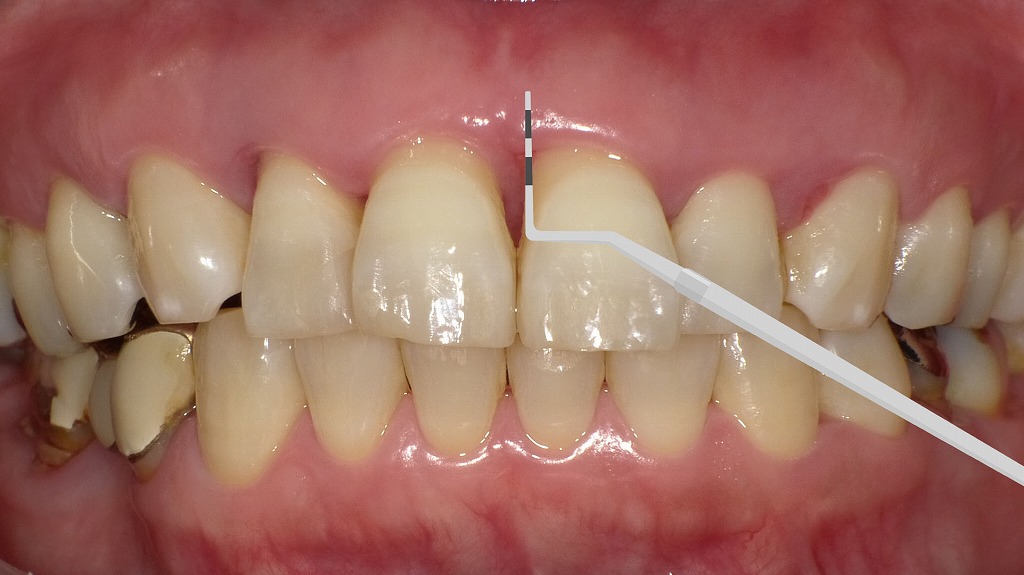

📌 連結冠まわりに起きた歯周炎と出血

この写真は**左下1番・2番・3番が連結された硬質レジン前装冠**が装着された状態を示しています。補綴物の辺縁付近では、以下のような炎症所見が確認できます。

■ 補綴物(硬質レジン前装冠)の状態

- 3本が連結されており、連結部の清掃性がやや低下しやすい構造。

- 歯冠の形態は整っていますが、歯頸部の適合がやや甘い可能性があり、プラークが停滞しやすい状況が考えられます。

■ 歯肉の変化(炎症所見)

- 歯頸部周囲に**発赤(赤く腫れた状態)**がみられます。

- 歯肉縁に沿って軽度の腫脹があり、炎症によるむくみが出ています。

- 特に1番・2番の間、2番・3番間、および補綴物の辺縁付近で出血を伴う歯周炎が明らかです。

■ 疾患の推定:歯周病(歯肉炎〜軽度歯周炎)

- プラーク・バイオフィルムの停滞による歯肉炎が主体。

- 経過が長い場合、連結冠周囲の骨吸収を伴う歯周病に進行するリスクがあります。

- 出血が認められるため、炎症性変化が進んでいるサインといえます。

🦷 臨床的なポイント

- 連結冠の適合不良/段差 → プラーク停滞 → 歯肉炎症

- ブリッジ下部は清掃が難しいため、スーパーフロスや歯間ブラシによる清掃指導が必須。

- 歯肉炎が続くと長期的に歯周病へ進行し、補綴物の寿命を縮めるリスクがあります。

📌 45度の角度で歯肉溝を清掃するバス法の実践

この写真は、左下前歯部の歯周炎(出血)を改善するために、バス法による歯みがき指導を行っている場面を示しています。

■ バス法ブラッシングの指導

- 歯ブラシの毛先を歯肉溝(歯と歯ぐきの境目)に45度の角度で当てている様子が確認できます。

- 毛先を軽い力で細かく振動させ、

**歯肉縁下1〜2mmに付着したプラークを除去するためのブラッシング方法(バス法)**です。